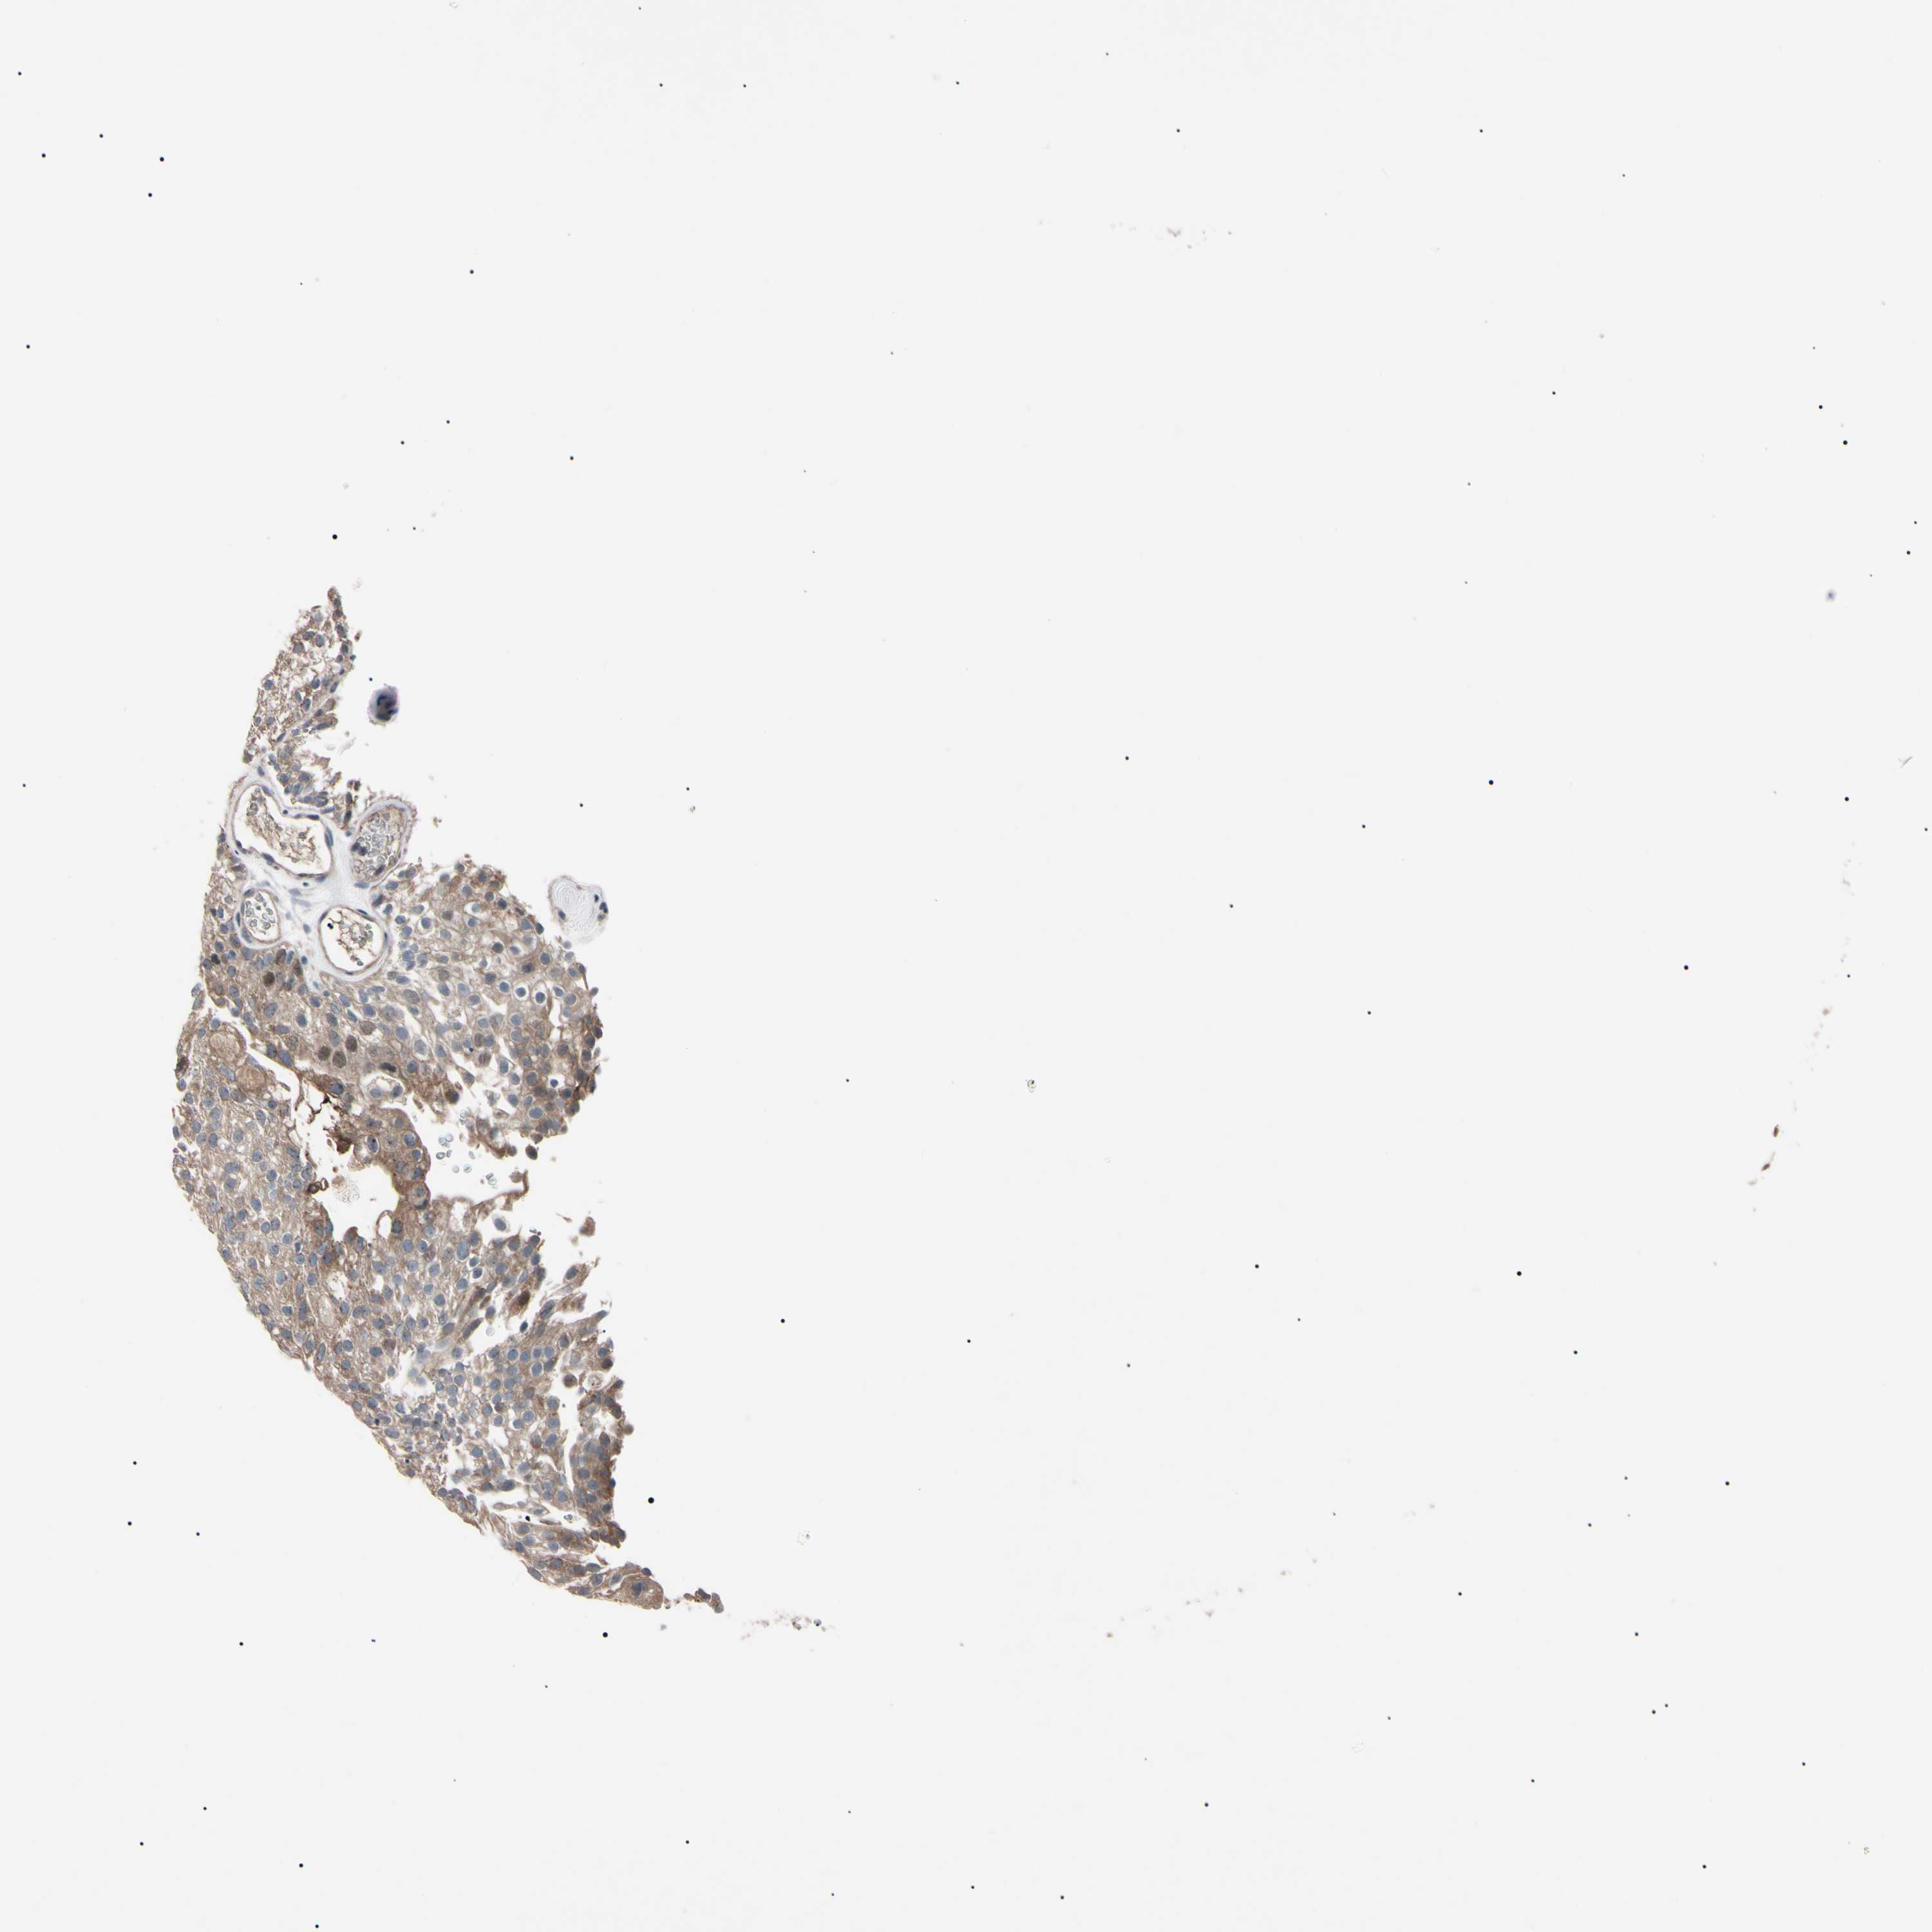

UROTHELIAL CANCER - Protein expressioni

A mouse-over function shows sample information and annotation data. Click on an image to view it in a full screen mode. Samples can be filtered based on level of antibody staining by selecting one or several of the following categories: high, medium, low and not detected. The assay and annotation is described here.

Note that samples used for immunohistochemistry by the Human Protein Atlas do not correspond to samples in the TCGA dataset.

Antibody stainingi

Antibody staining in the annotated cell types in the current human tissue is reported as not detected, low, medium, or high, based on conventional immunohistochemistry profiling in selected tissues. This score is based on the combination of the staining intensity and fraction of stained cells.

Each image is clickable and will lead to virtual microscopy that enables deeper exploration of all samples and also displays staining intensity scores, fraction scores and subcellular localization as well as patient and tissue information for each sample.

Antibody HPA008052

Antibody CAB010277

Urothelial carcinoma, Low grade

Urothelial carcinoma, High grade